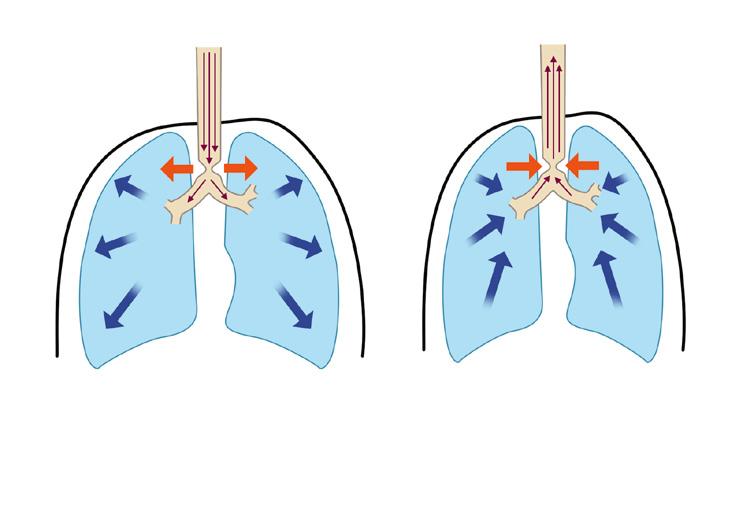

1.3.2 Obstrukce extratorakálních a intratorakálních dýchacích cest

Dýchací cesty probíhající uvnitř hrudníku a mimo něj podléhají naprosto odlišným mechanickým vlivům. V nádechu je přenosem negativního interpleurálního tlaku na plicní tkáň generován podtlak i v dýchacích cestách a zúžení horních dýchacích cest vlivem podtlaku obvykle progreduje. Naopak ve výdechu se pozitivní tlak v hrudníku přenáší i na dýchací cesty, čímž tento tlak převýší tlak atmosférický a obstrukci v horních dýchacích cestách zmírní (obr. 1.7a, b). Dýchací cesty uvnitř hrudníku jsou propojeny sítí elastických vláken s pleurou a během inspiria tak dochází k jejich pasivní dilataci. Výdech tento příznivý efekt ruší. V případě usilovného výdechu se dokonce v hrudníku generuje vysoký pozitivní tlak a zvláště u menších dětí s vyso-

Obr. 1.7 Schéma tlakových změn v nádechu (a) i výdechu (b) u extratorakální obstrukce dýchacích cest

(autorem obrázku je Jiří Hlaváček)

P aw – tlak v dýchacích cestách, Patm – tlak atmosférický

Schéma tlakových změn v nádechu (a) i výdechu (b) u intratorakální obstrukce dýchacích paw > patm

kou poddajností dýchacích cest vede k závažnému zhoršení intratorakální obstrukce (obr. 1.8a, b).

• Obstrukce extratorakálních dýchacích cest vede dominantně k inspirační dušnosti, naopak zúžení intratorakálních dýchacích cest vyvolá exspirační dušnost.